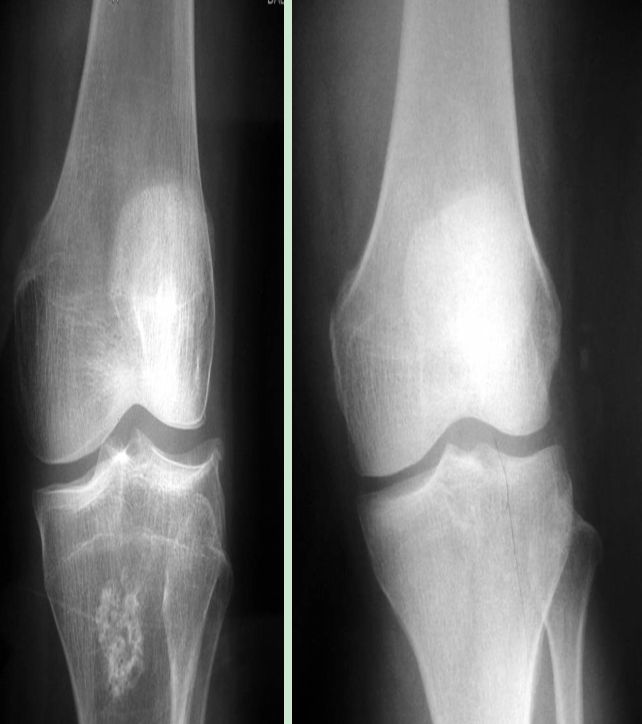

盤影半月板X線片的特征(60%)

高位腓骨頭(與脛骨平臺距離小于10mm,高于骨詬線可疑)。

外側(cè)脛股間隙大(寬、高),股骨外髁有一凹陷的壓跡(大于1mm)、扁平。

外側(cè)脛股間隙外緣骨質(zhì)增生(一般外側(cè)穩(wěn)定,不增生)。

可見左側(cè)高位腓骨小頭、外側(cè)脛骨增生、外側(cè)關(guān)節(jié)間隙較寬高

左側(cè)股骨外髁壓跡大于1mm